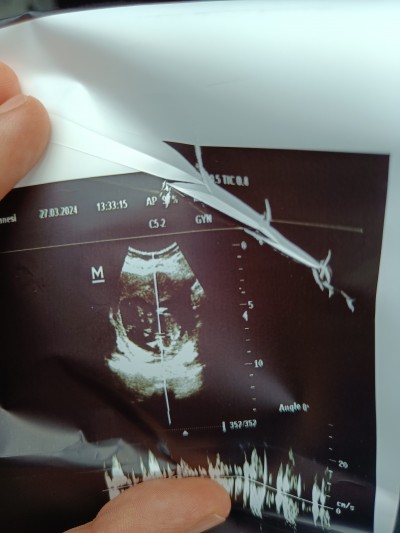

Kızlar bugün hem devlete gittim hem özel bı kliniğe . Devlet hastanesi büyük ihtimalle erkek dedi bacak arası çekti kağıdı. Özel de Yok kız dedi anlamadim kafam çok karışık. Foto aticam her iki doktoru da anlayan bakabilir mi ?